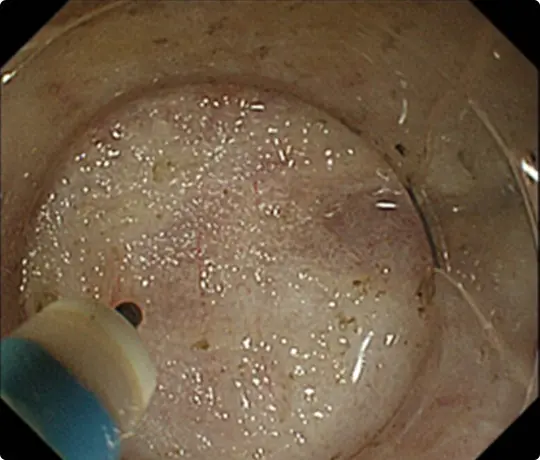

生理食塩水の中で行うESDです。水中では光の反射による視野障害がなくなり、自然な拡大効果もかかるため、鮮明な視野が得られます。

ケースバイケースで従来のESDと使い分けています。

この方法は2018年に当科が原著形式の英語論文として発表し、消化器内視鏡のトップジャーナルであるGastrointestinal Endoscopy(GIE)に掲載されました。

全国的にもまだ出来る病院が少ない十二指腸ESDを提示します。十二指腸ESDではUnderwater ESD(生理食塩水の中で行うESD)が有効です。

約25mmの十二指腸腫瘍を認めます。

病変の範囲を診断し、周りに電気メスでマークを付けます。

粘膜の下に液体を注入して病変を浮かせます。

マークの外側の粘膜を電気メスで切開。

粘膜の下の組織(粘膜下層)を電気メスで剥がしているところです。

十二指腸の粘膜下層は非常に薄く筋層を損傷し穿孔するリスクが高いとされています。

Underwater ESD(生理食塩水の中で行うESD)を行うことで光の反射がなくなり、拡大効果もあるため、精密に剥離することが可能になります。

穿孔(壁に穴があくこと)などの問題なく、病変を切除しました。

切除後は潰瘍が出来ますが、1~2ヵ月で治ります。十二指腸ESD後は、遅発性穿孔予防のため、クリップなどで治療後の潰瘍を完全に閉じるようにしています。

切除した検体をピンで伸ばして、ホルマリンで固定後、病理診断を行います。中央に見える赤く隆起している部分が腫瘍です(青い色素をかけています)。

病理診断で腫瘍は完全に切除されており、治癒と判定されました。